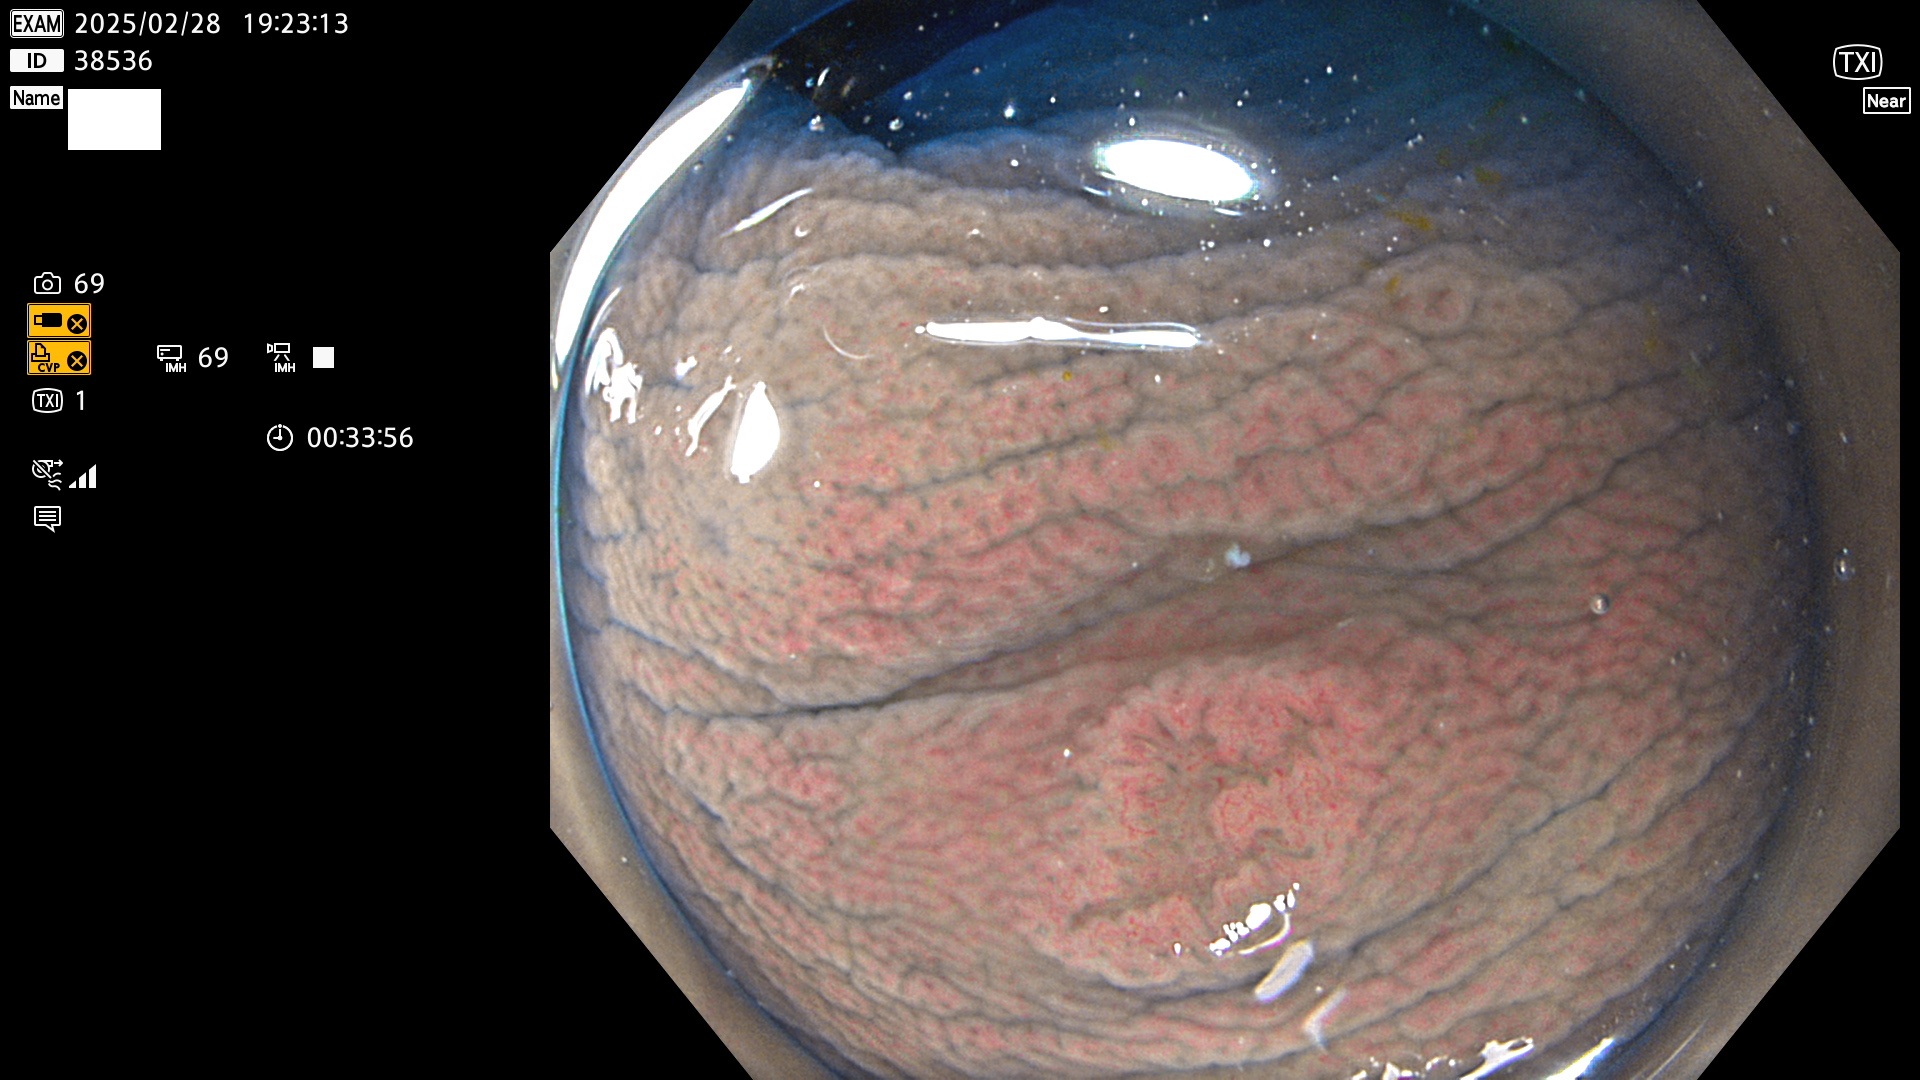

今週のUb、Uc型腺腫

完全に平坦な物をUb、陥凹している物をUcと呼びます。最も発見が難しく危険な病変です。

毎週の検査(木・金・土・日)に発見されたUb、Uc型・腺腫を、その週の日曜の夜にUPし1週間、提示します。

抽出の対象期間 2025年2月27日〜3月2日の4日間(48件の検査)9個 (9/48=19%)